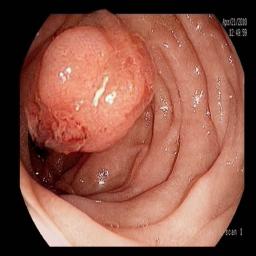

The performance metrics for Edgeconnect and AOTGAN on the validation data after fine-tuning the models, are shown in Table II. In addition to qualitative evaluation, Figure 3 provides example data from the different steps of the PolypConnect pipeline using the EdgeConnect model and the AOTGAN model. Due to obvious visual differences in the generated polyps between the models, we selected the EdgeConnect model as the main polyp inpainting model of the PolypConnect pipeline for further evaluation and qualitative assessment by domain experts.

Figure 3: Sample data used and generated in the different steps of PolypConnect pipeline. (a) - real polyp images, (b) - manually annotated polyp masks, (c) - randomly selected colon images used as input to the final step of PolypConnect, (d) - extracted edge images of row c. (e) - extracted edge images of polyp regions of row a using the masks of row b. (f) - combined edge images of row d and f. (g) - generated polyp on the images of row c using EdgeConnect. (h) - generated samples from AOTGAN.